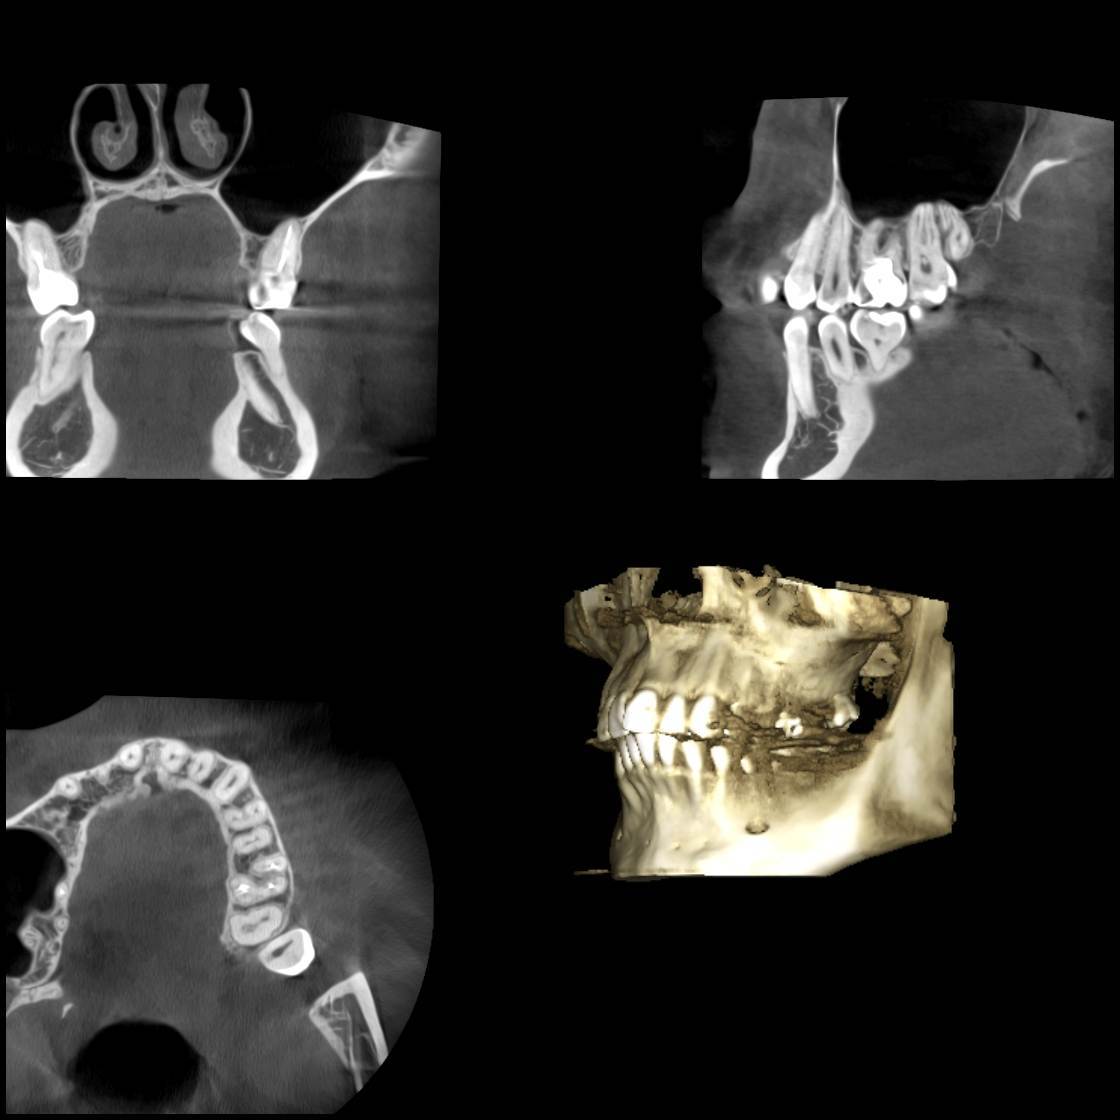

Дарья21 Опубликовано 9 февраля, 2025 Поделиться Опубликовано 9 февраля, 2025 Здравствуйте! Такая проблема…В сентябре лечила зуб, удалили каналы, запломбировали, поставили штифт. С того дня болит этот зуб не прерываясь каждый день. Каждый день приходится пить обезболивающие. Сделала кучу снимков, в том числе 3д снимок, врачи разводят руками, говорят, что на снимке всё в норме. Пробовала подтачивать пломбу, пила антибиотики, ходила на физиопроцедуры, полоскала разными травами. Боль никуда не уходит и не утихает. Стоматолог еще в октябре сказала: «Нет смысла лезть туда и еще раз пломбировать, так как по снимку всё в норме». Но прошло уже 5 месяцев, невозможно с этой болью жить… Подскажите пожалуйста, что это может быть и что делать, снимок прилагаю. ( Зуб 26) Заранее спасибо! Ссылка на комментарий

сирена Опубликовано 13 февраля, 2025 Поделиться Опубликовано 13 февраля, 2025 Выложите сюда кт (3D снимок), я думаю, что может болеть этот зуб. Полгода пить лекарства это ненормально. Ссылка на комментарий

wladdX Опубликовано 25 февраля, 2025 Поделиться Опубликовано 25 февраля, 2025 Коллеги, может есть ещё один к\канал в медиальном щёчном корне? Ссылка на комментарий

Carioznik Опубликовано 26 февраля, 2025 Поделиться Опубликовано 26 февраля, 2025 21 час назад, wladdX сказал: Коллеги, может есть ещё один к\канал в медиальном щёчном корне? Есть, мб2- пропущен 1 Ссылка на комментарий

Carioznik Опубликовано 26 февраля, 2025 Поделиться Опубликовано 26 февраля, 2025 (изменено) В 09.02.2025 в 06:00, Дарья21 сказал: Подскажите пожалуйста, что это может быть Исходя из КТ - у Вас есть один необработанный канал, т.е от туда "недоудален нерв"- скорее всего, в этом и причина. Вам лечили зуб используя оптику (увеличительные очки или микроскоп)? Изменено 26 февраля, 2025 пользователем Carioznik 1 Ссылка на комментарий

wladdX Опубликовано 27 февраля, 2025 Поделиться Опубликовано 27 февраля, 2025 (изменено) На КТ кариеса зуба 28 я не увидел. То что можно принять за кариозную полость на фото с экрана компьютера - полость зуба. Зуб имеет наклон в щёчном направлении около 30-40 градусов. Формирование корней у него завершено, так что дальнейшее его прорезывание маловероятно, скорее всего он останется в таком положении. Изменено 27 февраля, 2025 пользователем wladdX Ссылка на комментарий